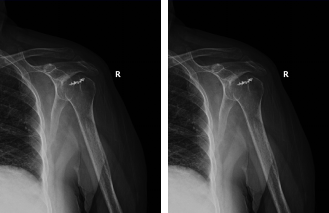

術(shù)前患者肩關(guān)節(jié)功能情況

術(shù)后4個月患者肩關(guān)節(jié)功能情況,患者恢復(fù)滿意